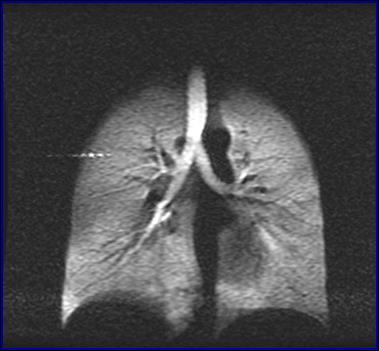

武汉物理与数学研究所研究员周欣、中科院院士叶朝辉带领的科研团队克服技术难关,研制出具有自主知识产权的人体肺部气体磁共振成像系统。该系统弥补了传统磁共振成像不能检测肺部空腔结构的缺陷,成功“点亮”人体肺部,且能同时获得肺部气气、气血交换的功能信息,成为肺癌等重大疾病早期科学研究和诊断的新利器。目前,该成果已转移转化成立产业化公司,且正在申请医疗器械注册证。2018年7月在同济医院建立了第一个肺部气体磁共振临床检测中心,用于大规模临床病例获取工作。

左:核心装置超极化气体发生器 右:我国首幅人体肺部气体磁共振成像图